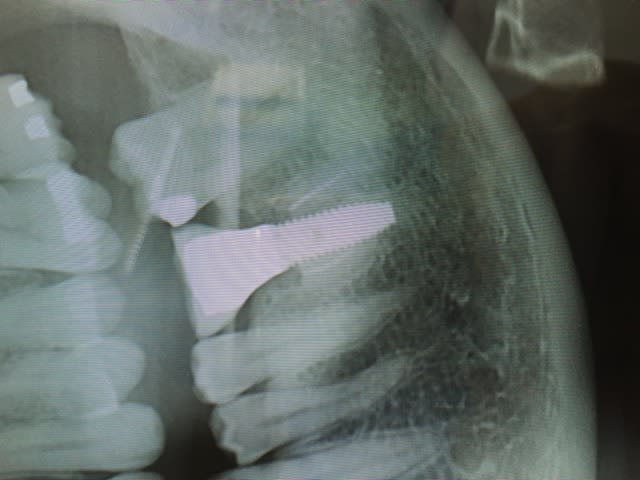

type de merdes faites par un dentiste qui n'ose pas dire " cette dent est cuite"

T'es sérieux ou ironique là ? Cette radio est intrigante. Soit on a à faire à un branlo complet, soit c'est un implanto blasé qui réinvente la roue, mais quoi qu'i en soit je trouve ça tordu....